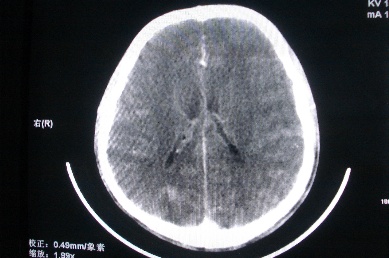

以下是引用zhangzhongshou在2007-4-18 17:49:00的发言:[br]脑实质内多发高密度结节影,支持肉芽肿得诊断,究竟是结核性、真菌性或寄生虫性的需结合临床,进一步检查确诊,但从影像上无法鉴别,只是临床上结核性肉芽肿最为多见而已。

以下是引用jiangjing在2007-4-18 16:57:00的发言:[br]考虑 感染性肉芽肿[结核可能性大],囊虫待排